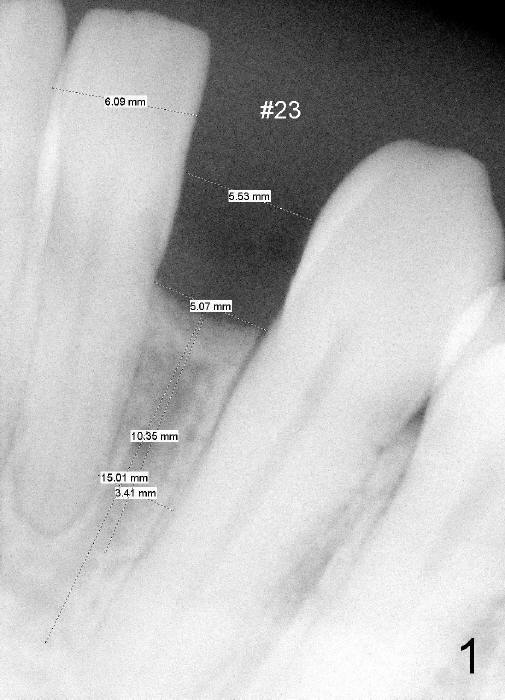

Fig.1: A 44-year-old black lady (dentophobic) requests implant restoration for #23, a congenital missing incisor post orthodontic treatment. The space between the roots of the neighboring teeth is 3.41 mm.